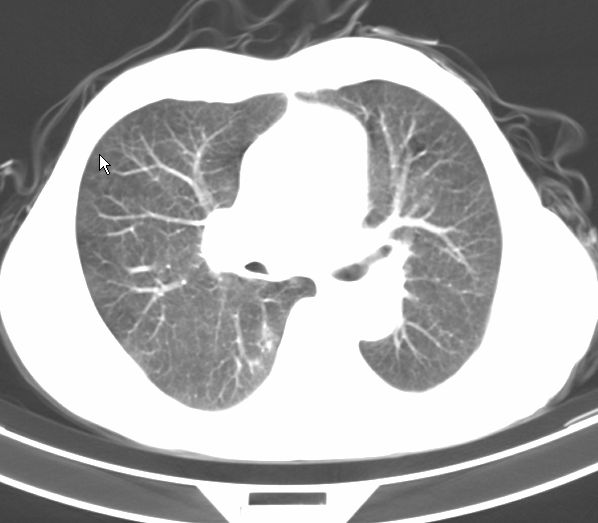

标题: CT17095:胸部病变请大家看看是什么性质的

请大家看看是什么性质的。炎性病变首先考虑哪一种炎症。

支持右肺上叶前段\\下叶内基底段感染,建议抗炎治疗后复查,除外结核.

支持右肺上叶前段\\下叶上段感染,建议抗炎治疗后复查,除外结核.

支持右肺上叶前段、下叶内基底段感染,建议抗炎治疗后复查,除外结核.

右肺上叶前段及下叶内基底段感染性病变;建议抗炎治疗后复查。

楼主说是炎症,凭啥?典型的周围型肺癌(腺癌可能性大),肝内可能已有转移,强化看看吧。